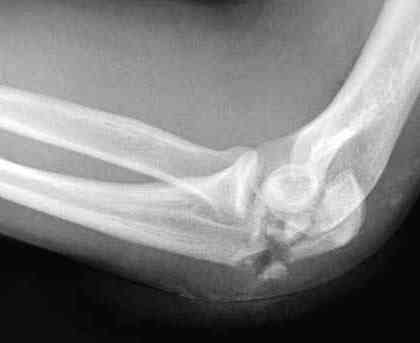

Good day dears colleagues! You presentated only one x-ray proection - lateral- of elbow.Accorden this I thing that this isn't avulsion fracture of olecranon,as usually can to see.This is Monteggia like fracture with subluxation of radial head.If

you can show AP x-ray or more more better CT elbow

Снимок, действительно, "не очень". Но глядя на него почему-то возникает очень сильное ощущение, что там и венечный отросток сломан тоже. Что ситуацию здорово усложняет. Причём перелом венечного "III типа" - очень крупный фрагмент, отломанный под самое его основание. А это (без фиксации) уже грозит задней, а возможно - и фронтальной (вальгусной/варусной) нестабильностью.

Это не перелом локтевого отростка! Безусловно сломан венечный отросток и, может оказаться, что и головка луча. Сложный перелом! Доступ задний, фиксация пластиной (LCP) и стягивающими винтами. Только не по Веберу! Положение больного на животе. ЭОП.

При самом большом к Вам уважении, Сергей Анатольевич, не соглашусь. У меня, после того, как добавили "прямой" снимок, сомнений не осталось. Венечный сломан наверняка. Но чтобы судить, насколько это критично для стабильности, нужно иметь строго боковую проекцию. И при этом помнить, что на него крепятся медиальные связки.

Прикрепляю снимок, где обведен фрагмент, несущий на себе венечный отросток (весь он смещён с этим фрагментом или частично - без качественной боковой проекции судить сложно), и отдельно на снимке обведено "ложе", от которого он сместился.

Почему я в данном случае против Вебера (хотя обычно горячий сторонник)? Да потому, что спицам нередко не хватает жёсткости, чтобы удержать предплечье от волярного подвывиха. При таком оскольчатом переломе спицы порой просто "прогибаются" за счёт одного только натяжения проволочной петли и головка луча может уйти в волярный подвывих (может, конечно, и не уйти). Но я бы предпочёл фиксировать всё к жёсткой пластине (включая фрагмент с венечным отростком) и, по возможности, исключить послеоперационную внешнюю иммобилизацию. Накладывать на такой локоть после операции гипс -- означает обрекать его на тяжёлую контрактуру.

Головка луча, кстати, на мой взгляд цела.